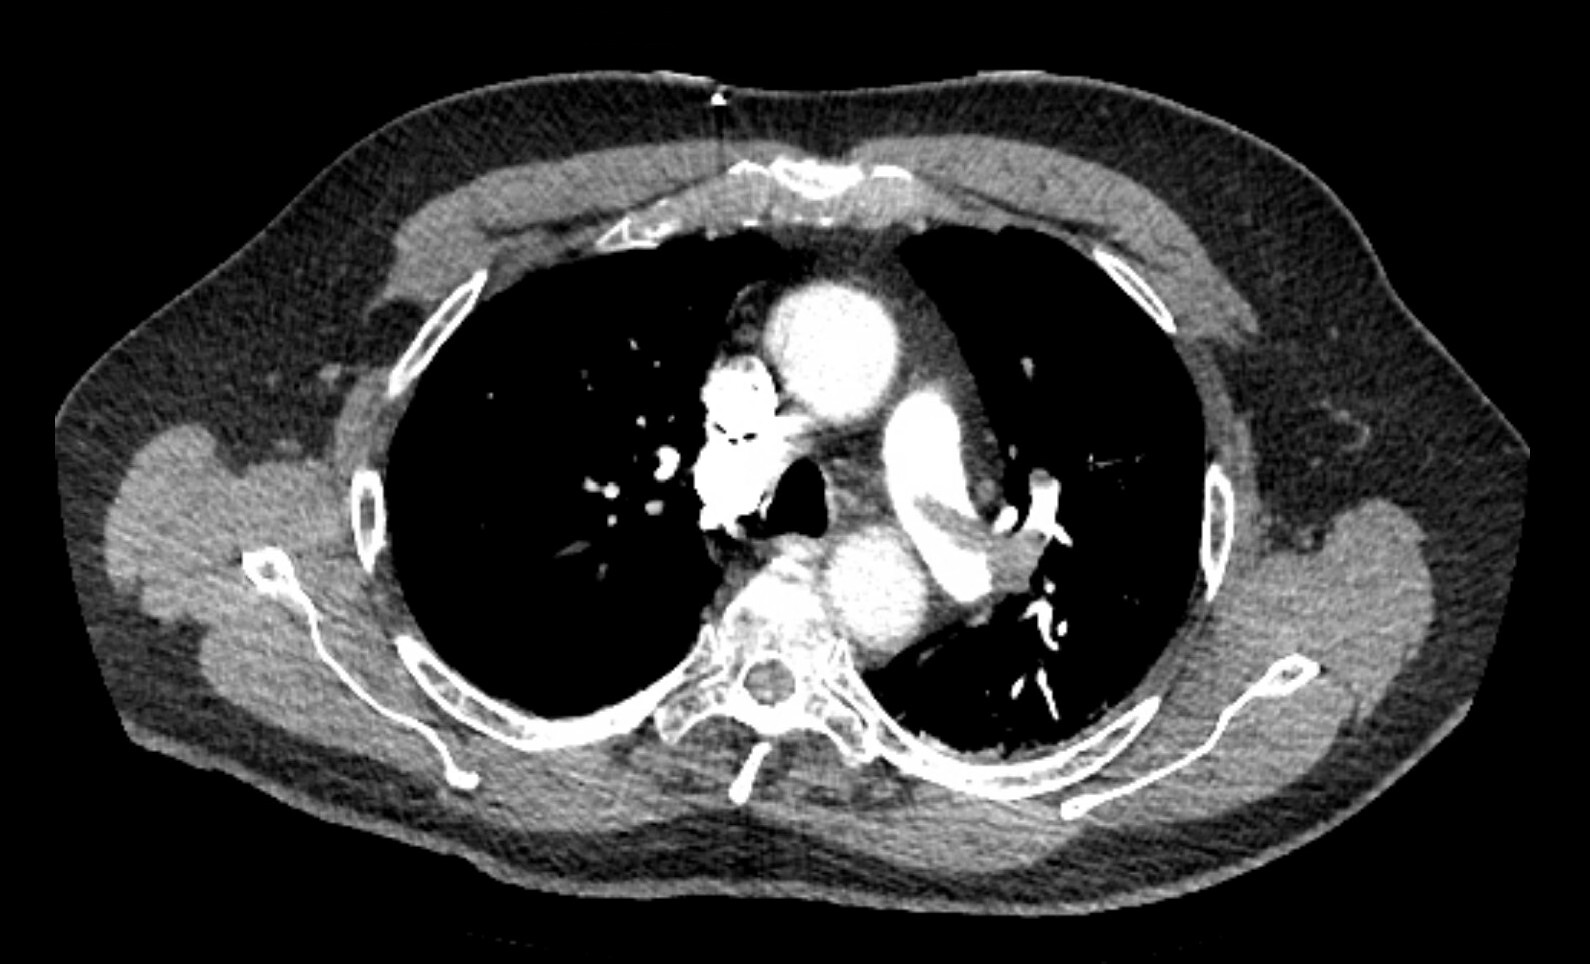

A 61-year-old woman with a history of hyperlipidemia, hypertension, stage 1 chronic kidney disease, and a baseline creatinine level of 1.5 mg/dL (132.6 μmol/L) presented yesterday with acute hypoxic respiratory failure from multilobar pneumonia. She underwent intubation last night, after which she developed mild shock, and she currently is receiving a 0.15 μg/kg/minute norepinephrine infusion. This morning, her ventilator settings have stabilized with assist control volume control with tidal volume of 350 mL, PEEP of 10 cm H₂Ο, and FiΟ₂ of 0.6. Her urine output has decreased, and she has been making only 5 to 10 mL of urine an hour for the last 12 hours. Her laboratory tests are notable for the results shown in Figure 1. Enteral feeding was started this morning at a trophic rate of 10 mL/hour.